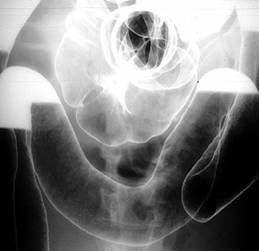

Examenul baritat cu dublu contrast evidentiaza ulceratiile aftoide sub forma unor mici depozite de substanta de contrast inconjurate de un halo transparent. Mai pot fi evidentiate leziuni unice sau multiple despartite de zone sanatoase- aspectul de "pietre de pavaj", stenoze pana la "semnul sforii", fistule. Cand exista suspiciunea de stenoza, examenul baritat este contraindicat.

Boala Crohn- ulceratii extensive Semnul

sforii in boala Crohn

ale peretelui colonului, inflamatia mucoasei ileala